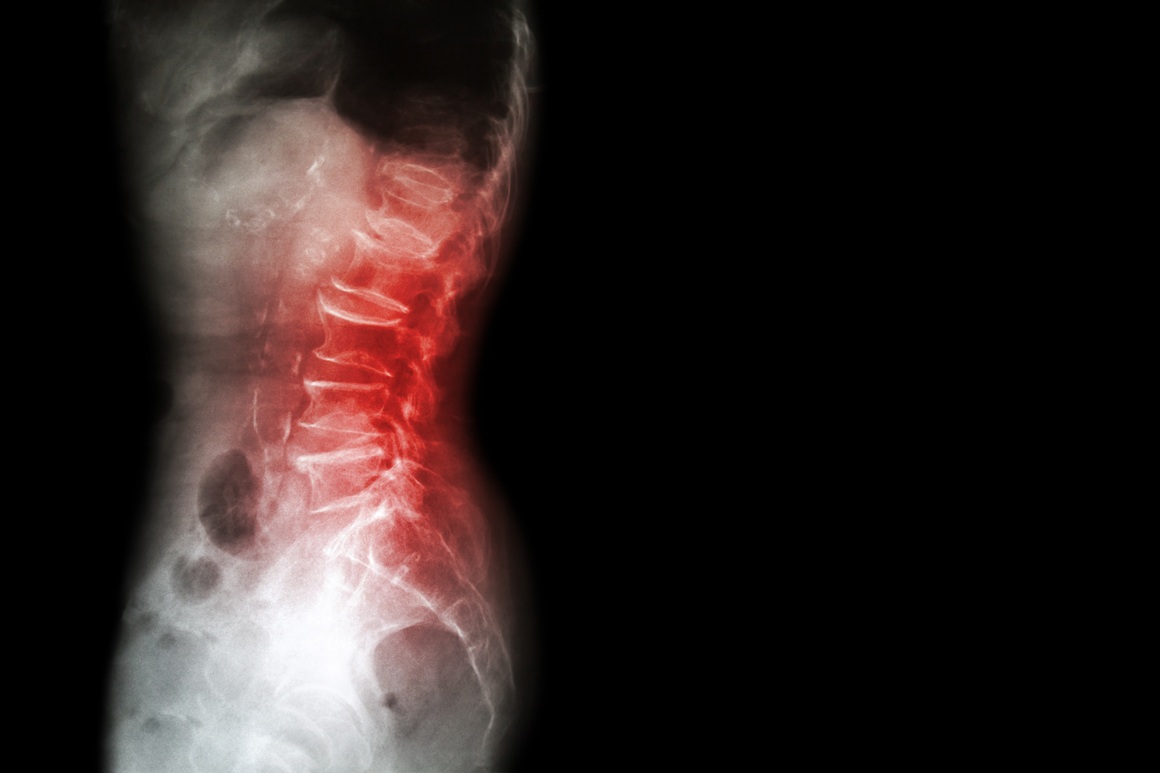

Psorijatični artritis je kronična upalna bolest koja može zahvatiti bilo koji zglob u tijelu, ali i mjesta gdje se tetive i ligamenti hvataju za kost. Kada upala zahvati zglobove kralježnice, govorimo o spondilitisu ili aksijalnom spondiloartritisu.

Ako su zahvaćeni zglobovi između kralježnice i zdjelice (sakroilijakalni zglobovi), stanje se naziva sakroileitis. Upala u tim područjima može dovesti do:

- bolova u donjem dijelu leđa

- ukočenosti kralježnice

- smanjene pokretljivosti.

Slikovne pretrage, poput rendgena i MR-a, pomažu liječniku razlikovati ova stanja jer postoje suptilne razlike u izgledu promjena na kralježnici i sakroilijakalnim zglobovima.